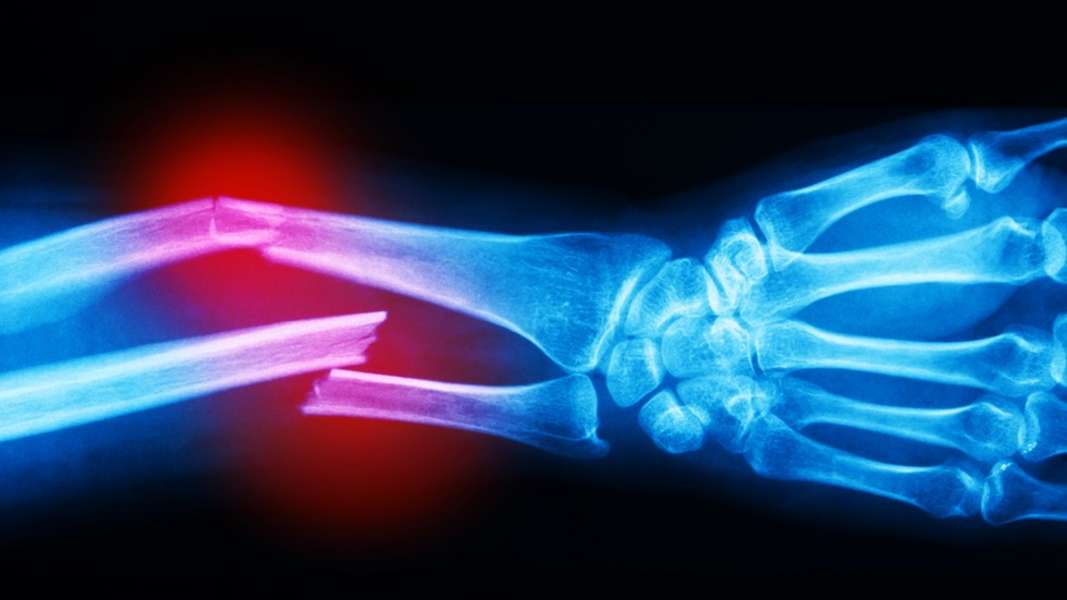

A mantis shrimp's carapace (the hard, thick shell that covers crustaceans and some other species) covers only. Also depends upon deflection or resistance of object struck. The eardrum may rupture at pressures above 35,000 pascals (35 kpa, or 5.08 psi) but is normally at higher levels, closer to 100,000 pascals (100 kpa or 14.5 psi). But they did measure those of his. But assuming an explosion goes as well as it can, the human body is quite resilient, able to withstand a surprising amount of force without instant death. Doing so increases the space between the sand particles, allowing them to move among each other more freely. The human body can survive relatively high blast overpressure without experiencing barotrauma. This can all be achieved by simply holding the tool above the surface. See enclosure (1) for two acceptable methods of meeting this requirement. Acetylene is a very dangerous gas. It takes more force to fracture the femur, bir noted — maybe. To measure it, an object that approximates a human head and neck (about 20 sq. The threshold for lung damage occurs at about 15 psi blast overpressure.